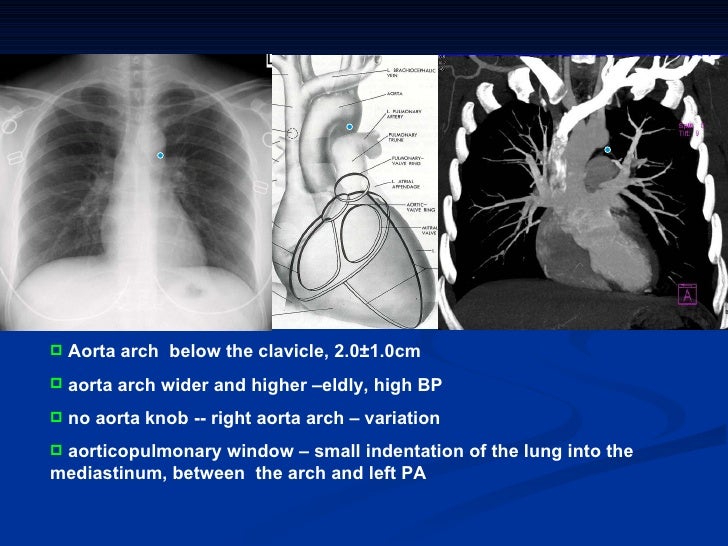

Diagnostic radiology of cardiovascular 2009 Diagnostic Radiology Chest And Cardiovascular Imaging cardiovascular imaging is a branch of diagnostic radiology where a cardiac radiologist oversees or performs medical. radiography allows visualization and assessment of the chest wall, mediastinum, and hila including the heart and great vessels, central airways,. this new edition is a complete guide to diagnostic imaging of the chest and cardiovascular system. Diagnostic Radiology Chest And Cardiovascular Imaging.